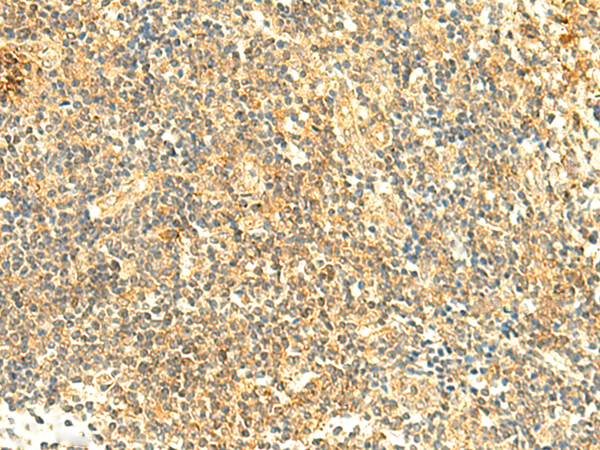

分类: 科研抗体货号: P10061别名: Ntra; KILON; IGLON4; DMML2433应用: WB,IHC反应种属: Human, Mouse, Rat